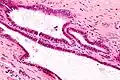

| High magnification micrograph of endosalpingiosis, showing the characteristic cystic spaces lined by a simple epithelium with cilia. H&E stain. | |

It is characterized by cysts with tubal-type epithelium (e.g. ciliated epithelium) surrounded by a fibrous stroma. It is not often associated with hemorrhage.